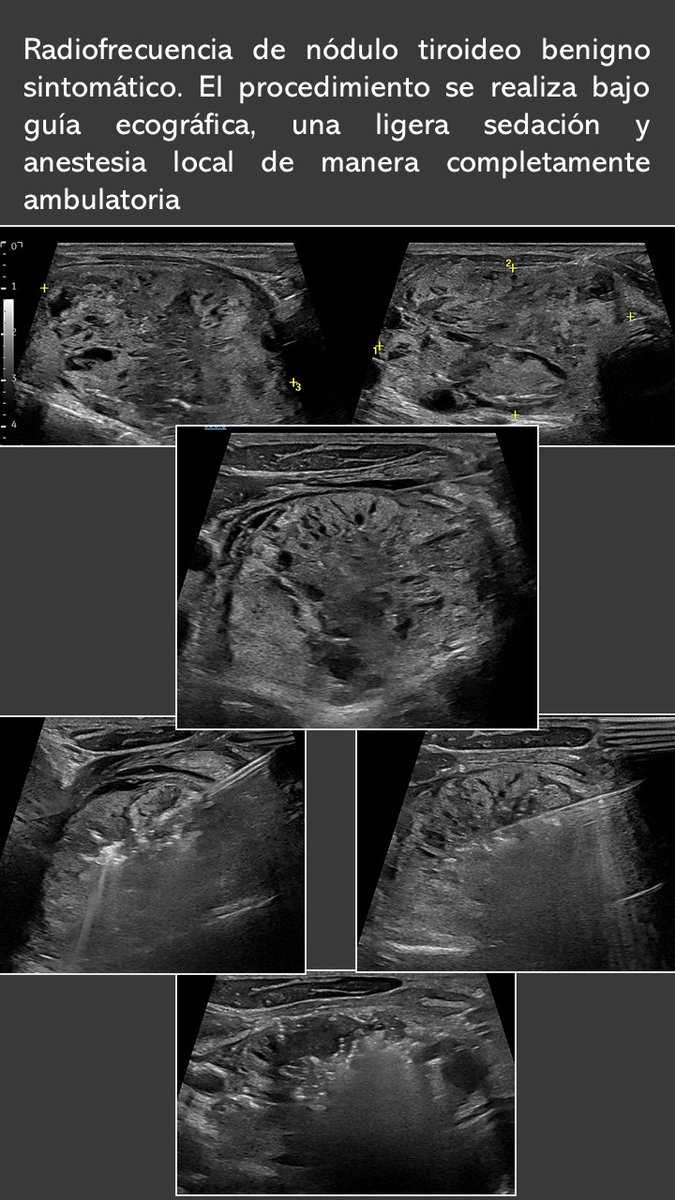

¿Tratar quistes y #nódulos #tiroideos sin cirugía? Gracias a técnicas como la etanolización o la radiofrecuencia, endocrinólogos y radiólogos intervencionistas trabajamos juntos en Clínica Universidad de Navarra para ofrecerte el mejor tratamiento personalizado y mínimamente invasivo.